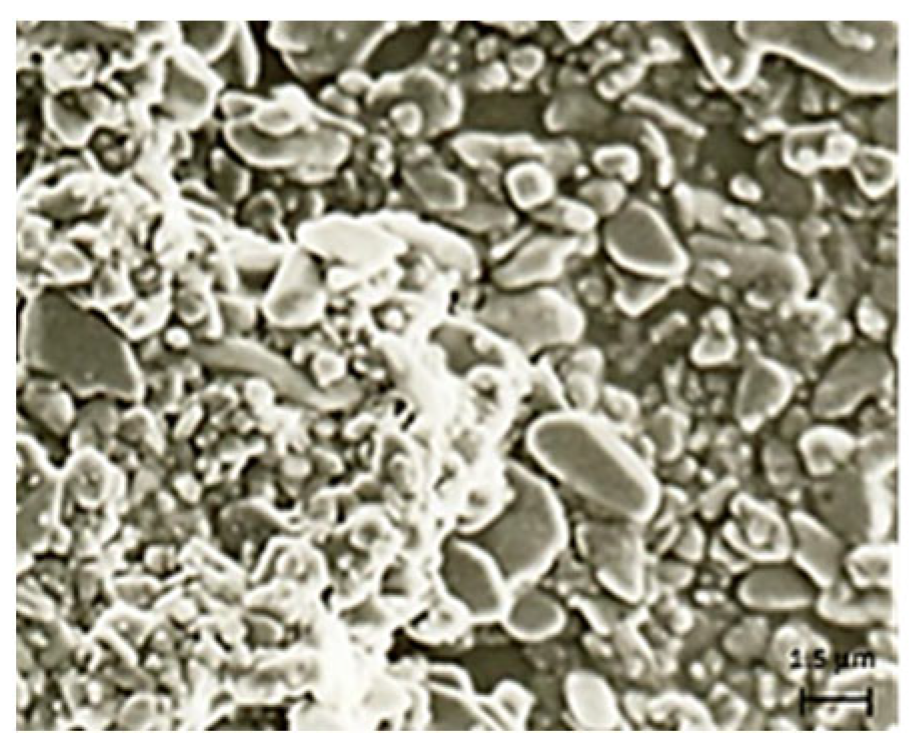

2.4. Microspheres Characterization